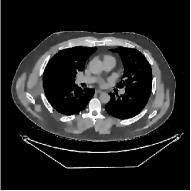

This section compares the reconstruction quality and runtime among the proposed MBIR method, PWLS-ST-, and other three MBIR methods, PWLS-EP, PWLS-DL, and PWLS-ST-. Table I shows that, for both 2D and 3D sparse-view CT reconstructions of the XCAT phantom, the proposed PWLS-ST- model outperforms PWLS-EP and PWLS-ST- in terms of RMSE. In addition, PWLS-ST- using a square transform (of size ) achieves lower RMSE than PWLS-DL using an overcomplete dictionary (of size ) for 2D sparse-view reconstructions. Fig. 3(a) and Fig. 4 show the reconstructed images for 2D and 3D phantom experiments, with different reconstruction models and different number of views. (See the corresponding error maps in the supplement.) The proposed PWLS-ST- consistently gives more accurate image reconstructions compared to other MBIR methods. Specifically, PWLS-ST- has smaller errors in the heart region (see zoom-ins in Fig. 3(a)) of 2D reconstructions than PWLS-DL and PWLS-ST-. In addition, compared to PWLS-ST-, PWLS-DL and PWLS-ST- have some ringing artifacts around the edges with high transition, e.g., edges between air and soft tissues. (See a comparison of profiles of PWLS-ST- and PWLS-ST- in the supplement.) In particular, PWLS-ST- and PWLS-DL give more visible ringing artifacts for 2D reconstruction from fewer views, and PWLS-ST- has these ringing artifacts for 3D reconstructions regardless of the number of views (see zoom-ins in Fig. 4). Table II reports runtimes of different MBIR methods in reconstructing the -views XCAT phantom scan. (FBPConvNet is a non-MBIR method and its runtime for processing a image is approximately one second with a TITAN Xp GPU.) While providing better reconstruction quality, the proposed Algorithm 1 of PWLS-ST- has shorter runtime compared to the algorithms of PWLS-DL and PWLS-ST- in Section III-A. Similar to the PWLS-EP algorithm, the reconstruction time of the PWLS-DL, PWLS-ST-, and PWLS-ST- algorithms can be further reduced by using ordered subsets [51].

| (b) 3D axial cone-beam CT experiments |

Fig. 7 studies the influence of regularization parameters and on PWLS-ST-. Given a fixed hard-shrinkage parameter , a larger value better removes noise (or unwanted artifacts), but too large can oversmooth reconstructed images; compare Fig. 7(a) and Fig. 7(b). Given a fixed regularization parameter , a larger value leads to lower sparsity in sparse codes and achieves better noise reduction, but too large can remove some edges (e.g., in bone regions); compare Fig. 7(c) and Fig. 7(d). In particular, Fig. S.8 in the supplement shows that once the value is properly chosen, PWLS-ST- is robust to a wide range of values.